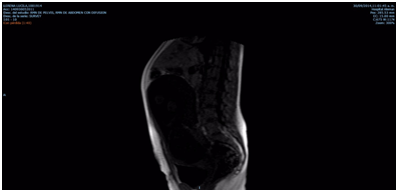

She could breastfeed the baby and she is still alive and her baby is going to turn on two years old. Obviously that her prognosis is possibly ominous in face of the future, but with this medical strategie, she survived, and the newborn was delivered close to term, is healthy and at least, is still under the care of his mother. On the other way round, we have had a very preterm newborn with all the problems attributable to extreme prematurity without any improvement in the mother´s health (Figure 1).

Figure 1 Liver: Focal images hypointenses in T1 and hyperintenses en en T2 related to MTS. Uterus: gestational uterus.